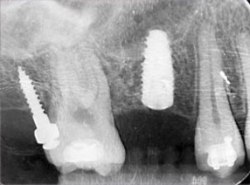

植牙治療過程

治療前

治療中